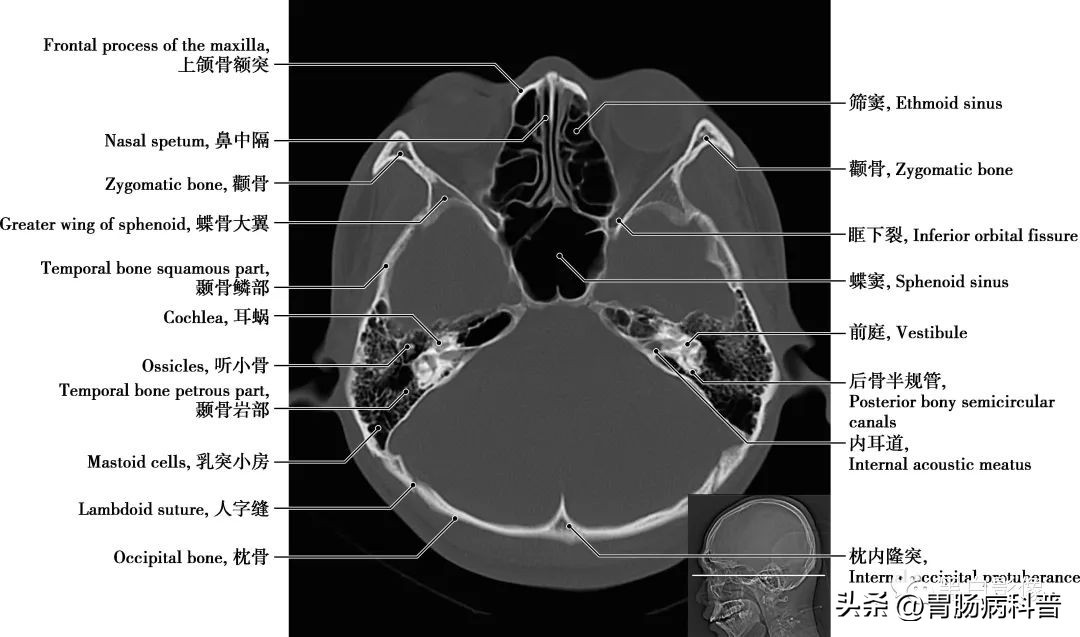

(二)骨窗轴位解剖图

图1-2-15 经第四脑室下部轴位切面

耳蜗 为内耳的一个解剖结构,和前庭迷路一起组成内耳骨迷路,是传导并感受声波的结构,位于骨前庭的前内侧,形似蜗牛壳,耳蜗的中轴称蜗轴,呈圆锥形,由一条骨蜗螺旋管环绕蜗轴旋转二又四分之三圈而成